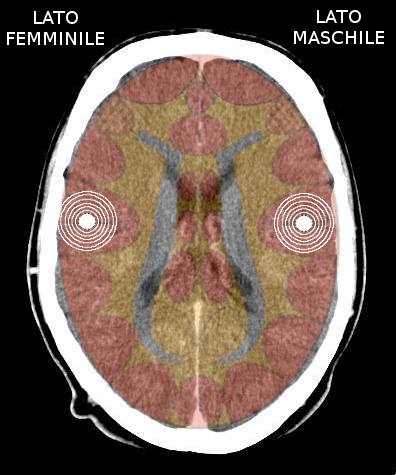

- Requisiti: Si è in costellazione schizofrenica quando due attivazioni colpiscono i due emisferi cerebrali di uno stesso livello:

- le due emiparti del tronco cerebrale;

- i due emisferi cerebellari;

- i due emisferi cerebrali (midollo e/o corteccia).

- NON È COSTELLAZIONE quando due attivazioni interessano due livelli cerebrali differenti, anche se occupano i due emisferi.